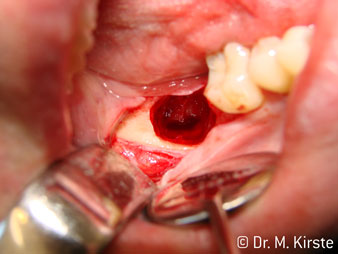

Die Winkelwahl des 45° Handstücks bringt viele Vorteile in der Anwendung. Chirurgisch tätige Kollegen, und für diese ist das Handstück in erster Linie entwickelt worden, werden schnell bemerken, dass man sehr gezielt arbeiten kann. Insbesondere bei der Weisheitszahnentfernung (Abb. 2) bedarf es keiner großen Weichteilabspreizungen im Wangenbereich (Abb. 3). Die Handstückkopfgestaltung kombiniert mit leichten Kopfdrehungen bei der Präparation lassen ein sicheres und schnelles Arbeiten im retromolaren Bereich zu.

Die professionelle Lagergestaltung im Innenleben des Handstückkopfes garantiert einen ruhigen Lauf der Bohrer, bei der Zahn- oder Wurzelseparation (Abb. 4 - 9) zeigt sich ein beeindruckendes Schnittbild ohne Schlageffekte.